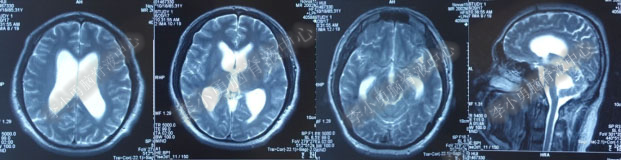

2016年5月9日因“间断性眩晕半月,恶心呕吐一周”以“梗阻性”脑积水,第1次住入北京某企业三级医院神经外科内镜组。2016年5月10日(入院后第2天)行头部MRI(图-1)检查示脑室系统扩张。

图-1:2016年5月10日头部MR